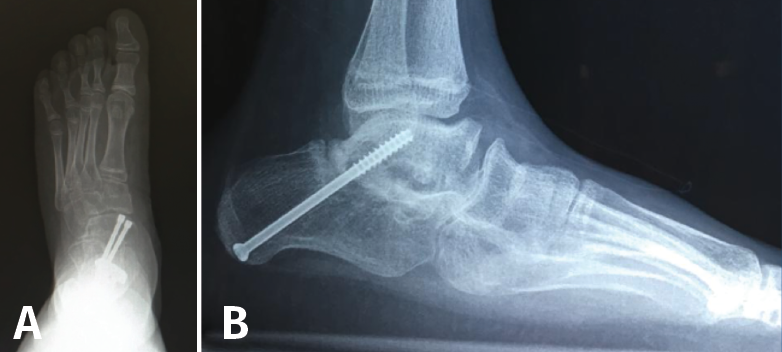

Artrodesis talonavicular

Se realiza por un abordaje medial, evitando lesionar la arteria pedia y el nervio peroneo profundo. Tras realizar una cuña de base plantar y medial, se realiza la artrodesis parcial correctora en aducción y pronación de la columna medial (Figura 15A).

Figura 15. Artrodesis del tarso. A: artrodesis talonavicular; B: artrodesis subastragalina.

Artrodesis subastragalina

La artrodesis subastragalina aislada tiene indicación en casos de pie plano rígido con deformidad predominantemente en valgo o en coaliciones tarsianas irresecables.

Al bloquear la articulación subastragalina, permanece un 26% de movilidad TN y del 56% en la calcaneocuboidea(15). Esta técnica es de elección en pacientes con menor demanda mecánica, debido a la potencial degeneración de las articulaciones adyacentes.

Esta artrodesis permite la restauración de la relación anatómica entre astrágalo y calcáneo. La fijación se suele realizar mediante tornillos calcáneo-astragalinos desde plantar a dorsal, en la posición corregida (Figura 15B).